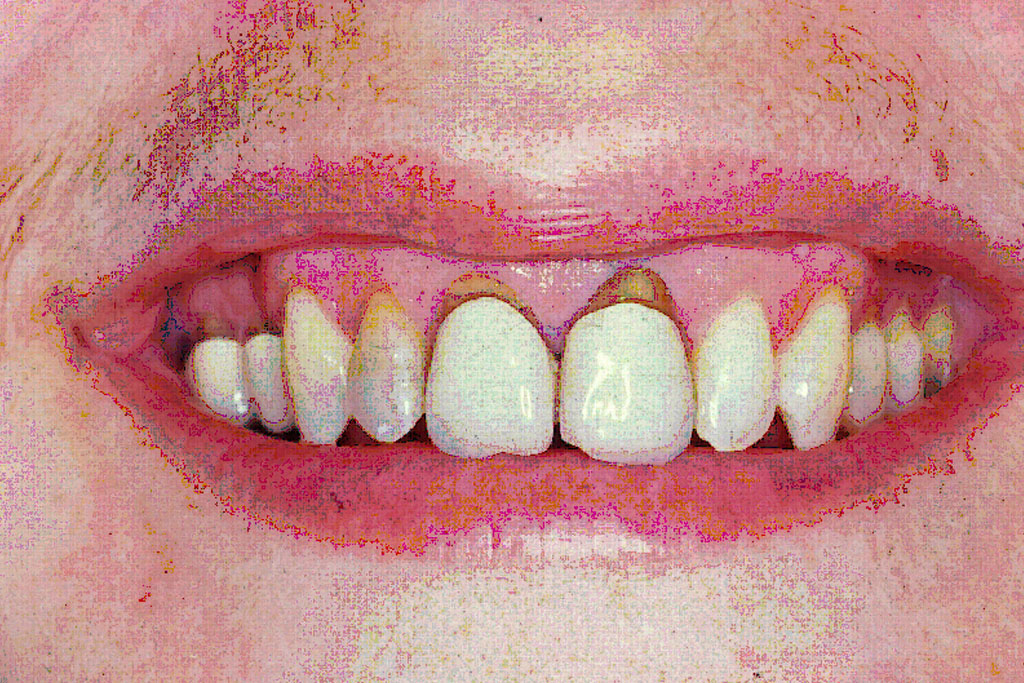

Die präzise Darstellung präparierter Zahnstümpfe auf dem zahntechnischen Meistermodell stellt auch heute noch eine der wichtigsten Schnittstellen zwischen Zahnarzt und Zahntechniker dar. In der Produktionskette hin zur fertigen Krone nimmt dabei der Zahnarzt eine entscheidende Schlüsselstellung ein. Nur er kann durch seine reproduzierbare und präzise Abformmethodik die Voraussetzung für ein perfektes Modell schaffen und damit Passungenauigkeiten der anzufertigenden Krone vermeiden. Dies ist besonders deshalb wichtig, weil Passungenauigkeiten an Kronenrestaurationen (Über- und Unterextension des Kronenrandes, übergroßer Randspalt ) häufig eine Fülle perioprothetischer und ästhetischer Probleme verursachen (Abb.1 ) :

Da die Präparationsgrenze bzw. der Präparationsrand in der Regel 0,5 bis 1,5 mm unterhalb des Zahnfleischrandes (= subgingival ) verläuft, wird zumeist während der Präparation des Zahnes das Zahnfleisch verletzt. In der Folge tritt eine verstärkte Blutung am Zahnfleischrand (= Sulkus) auf.

Bei der anschließenden Abformung der präparierten Zahnstümpfe bestehen zwei Probleme (Abb2.) . Zum Einen muss das den Zahn umgebende Weichgewebe vom Präparationsrand abgedrängt werden (= Retraktion) und zum Anderen darf während der Abformung kein Blut auf die abzuformende Zahnoberfläche gelangen. Unzureichende Retraktion und Blutungen im Sulkus verhindern eine präzise Abformung. Die Abformung muss wiederholt werden.

Mit Hilfe des Lasers können heute erstmals diese beiden. Hauptprobleme bestmöglich in den Griff bekommen werden.

Der Laser verdampft punktuell störende Gewebeanteile im Sulkus und stoppt gleichzeitig durch seine blutungsstillende Wirkung die Gewebeblutung . Dabei ist die Gewebeschädigung (=Trauma) minimal. Durch diese minimaltraumatisierende Wirkung ist die anschließende Wundheilung wesentlich schmerzärmer als bei der früher üblichen elektrochirurgischen Abtragung. Im Zuge der Heilung ist die Schrumpfungstendenz des Zahnfleischrandes zudem erheblich geringer. Dies fördert das ästhetische Erscheinungsbild der eingegliederten Krone im Zahnhalsbereich, da der Kronenrandbereich unterhalb des Zahnfleischrandes verbleibt (Abb. 3 ).

im Bereich der Vollkeramikkronen an den Oberkieferfrontzähnen 13-23